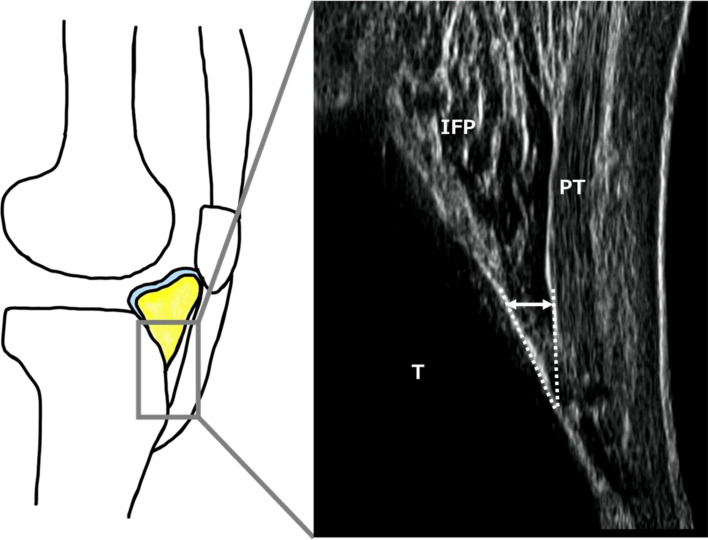

Methods: Twelve patients with knee OA, 12 healthy young volunteers, and 12 healthy elderly volunteers were recruited. The IFP was evaluated using ultrasonography, and dynamics were recorded in video mode during walking. The IFP value was identified as the thickness between the patellar tendon and proximal tibial line. The morphological change in the IFP (ΔIFP) was shown as the difference in IFP value between maximum and at initial contact on the waveform. Kinematics and kinetics data were evaluated using a three-dimensional motion analysis system synchronized with ultrasonography, and the knee flexion angle and its moment in the stance phase were evaluated.